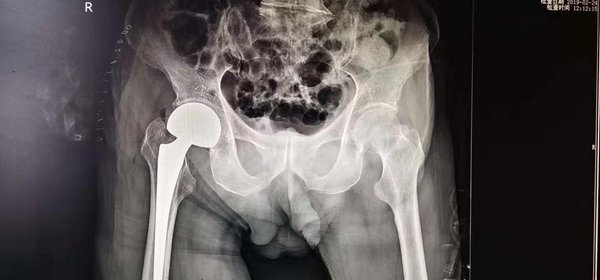

入院后,主管医生黄孝明向上级医生斯勇汇报后立即为老人进行了详细检查,发现除右侧股骨颈骨折外,还患有多种老年性基础疾病,肺部有感染,手术风险极大,有可能在术中术后死亡,无论采取保守治疗还是手术治疗,都存在很大风险。为慎重起见,骨科主任吴俊一向分管院领导杨林副院长汇报了相关情况,杨林副院长多次询问病情,组织骨科、麻醉科、呼吸科、心内科专家进行会诊,拟定了详细的治疗方案和各种预案,并邀请了成都市第一骨科医院的尹毅主任参加此次手术治疗。经过充分的术前准备后,成都市第一骨科医院的尹毅主任与我院骨科医生斯勇、韩志勇、宿瑞强一道于2019年2月23日给老人进行了"人工股骨头置换术"。凭借科学的手术方案、充分的术前准备和娴熟的医疗技术,经过手术团队和相关科室的密切配合,仅用20分钟成功完成手术,这是阿坝州人民医院迄今为止年龄最大的一例外科手术。2月24日,术后24小时张绍根老人在家属的搀扶下已经能下地站立,轻微活动。